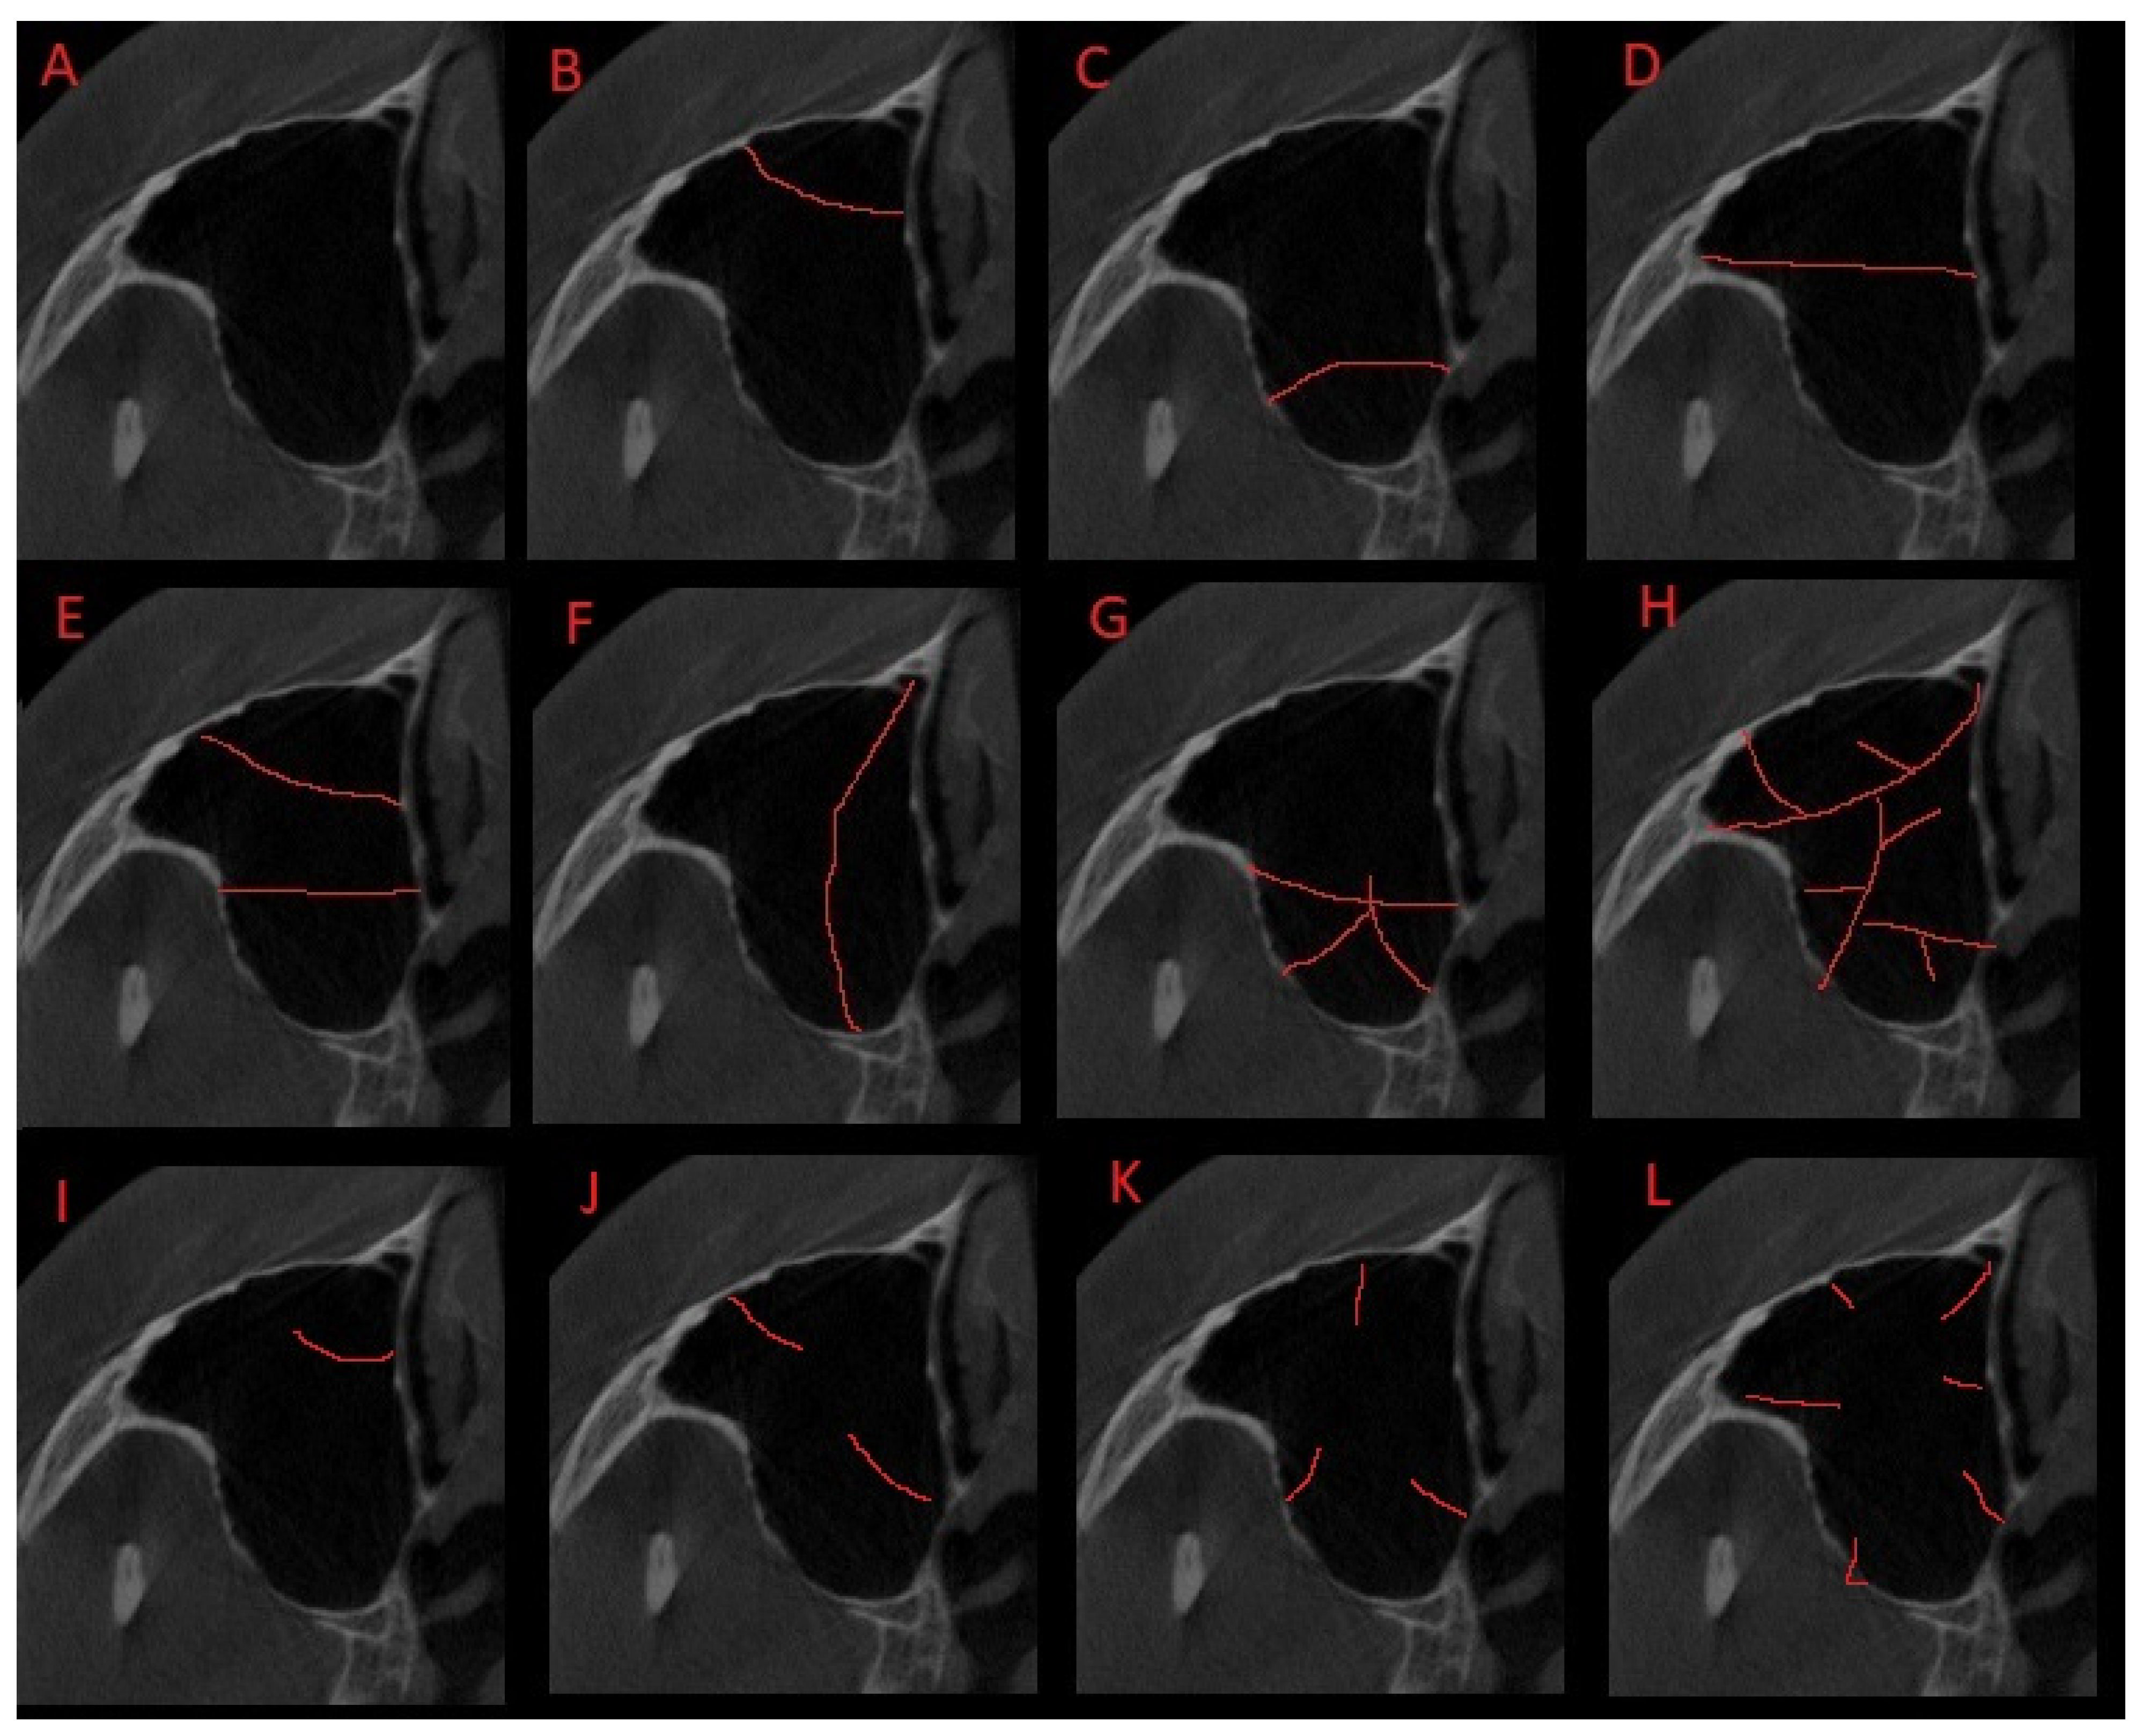

3.2. Classification Proposal

3.3. Clinical and Surgical Cosiderations

| Types of Classification | Number of Observations (Percent) |

|---|---|

| 41 (91.11) |

| 13 (28.89) |

| 7 (15.56) |

| 5 (11.11) |

| 3 (6.67) |

| 1 (2.22) |

| 9 (20.00) |

| 2 (4.44) |

| 0 (0.00) |